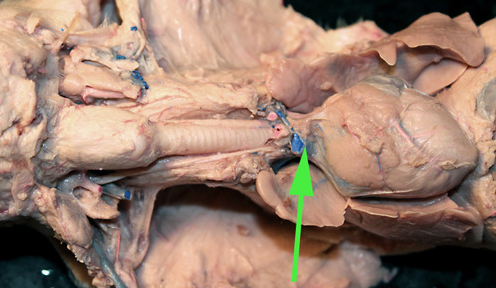

The vessel marked by the green arrow is a coronary artery